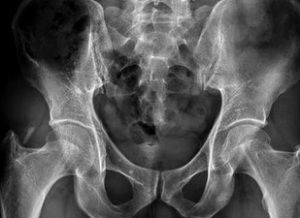

異位骨化是指在軟組織出現成骨細胞,並形成骨組織。多半發生在大關節周圍,例如髖關節、肘關節等。常見於神經癱瘓的患者。發病機理不清楚。誘發因素可能是神經和生物電因素。早期局部有明顯腫痛,關節活動受限。晚期由於骨組織形成,導致關節活動限制。

介紹 症狀 病因 治療肘關節骨化肌炎是肘部創傷嚴重和較常見的併發症,約占肘部骨折與脫位的3%。有明確外傷史;傷後反覆被動屈伸關節;一般傷後3~6周內有增大趨勢,6~8周后趨於穩定。

病因 臨床表現 檢查 參考資料,術後功能恢復快,異位骨化形成少,關節活動滿意,但此入路解剖複雜,要防止損傷...相似,但損傷較小,異位骨化發生率較低。髖臼骨折手術復位內固定治療的方法...創傷性關節炎的發生。 異位骨化術後發生了異位骨化,但程度較輕,髖關節的屈曲...